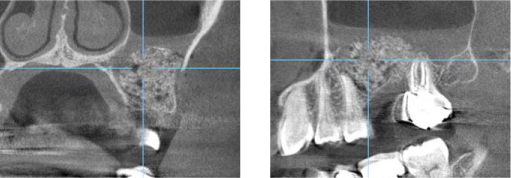

上顎洞までの骨の距離が極端に少ない場合(5mm以下)、上顎洞の横の骨に穴を空けて、骨を作る為の材料を入れていきます。 ソケットリフトより一度に大量の材料を入れることが出来るため、多くの骨を作る事ができます。 6か月経過し、骨が再生した事を確認した後、インプラントを埋入しますので、2回に分けてオペをする事になります。 ソケットリフトより患者負担は大きく、腫れ、痛みを生じやすい方法になります。

以下に、実際の症例を示します。